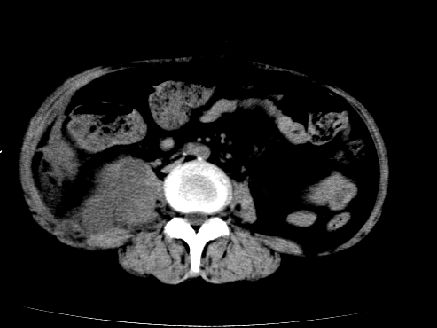

以下是引用liuyue在2008-7-19 10:17:00的发言:[br]考虑:1.肾周脓肿,肾实质、腰大肌及侧腹壁均受累及。 2.右肾囊肿。[br]建议:强化扫描,除外肾癌之可能。[br]

以下是引用zhengfaming在2008-7-19 14:48:00的发言:[br]右肾脓肿并感染可能性大,建议增强

以下是引用江广1996在2008-7-19 10:48:00的发言:[br]先考虑右侧肾周感染脓肿形成并累及腰大肌,右肾前侧有病灶考虑囊肿。